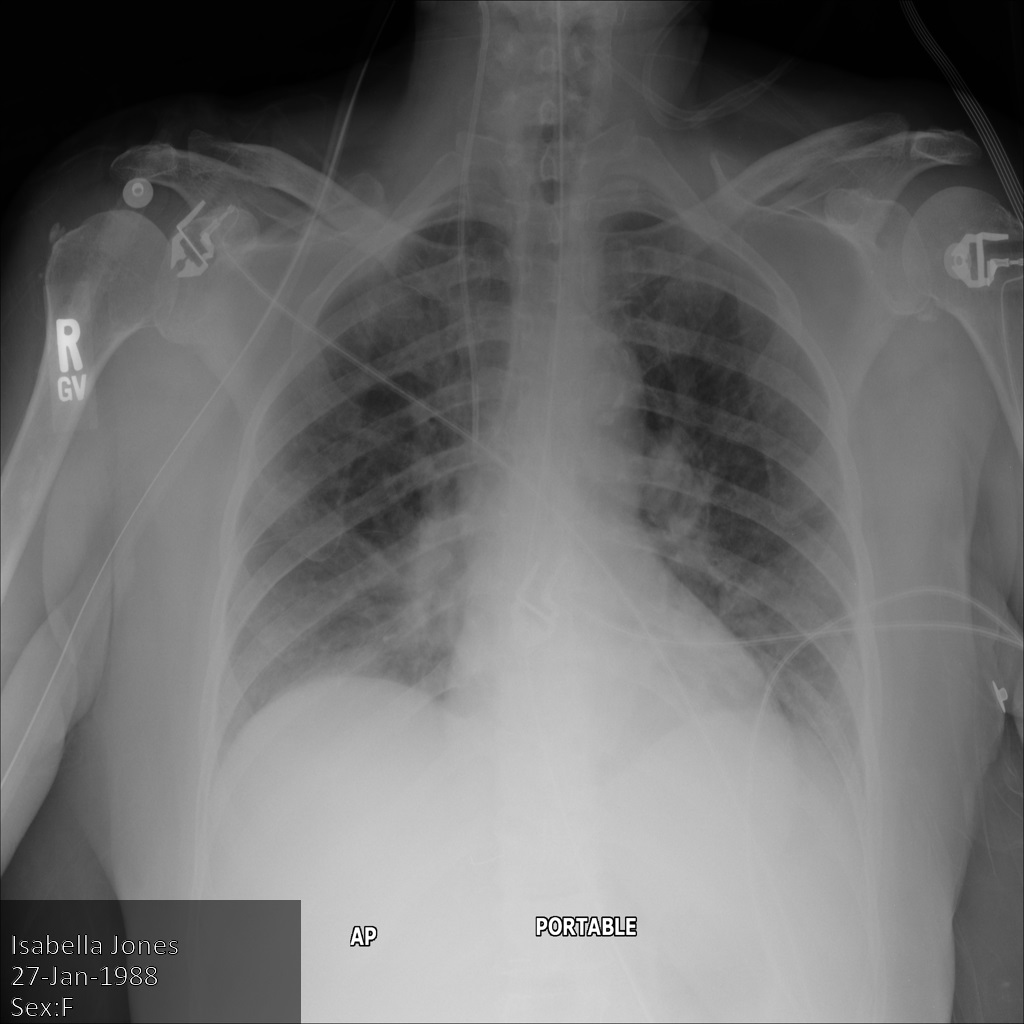

Cada uma das secções seguintes fornece exemplos de como remover a identificação dos dados DICOM usando vários métodos. É fornecida uma saída da imagem desidentificada com cada amostra. Cada exemplo usa a seguinte imagem original como entrada:

Pode comparar a imagem de saída de cada operação de desidentificação com esta imagem original para ver os efeitos da operação.

Depois de enviar a imagem para a Cloud Healthcare API, a imagem aparece da seguinte forma. Embora os metadados apresentados nos cantos superiores da imagem tenham sido ocultados, as informações de saúde protegidas (PHI) incorporadas na parte inferior da imagem permanecem. Para também remover o texto incorporado, consulte o artigo Ocultar texto incorporado em imagens.